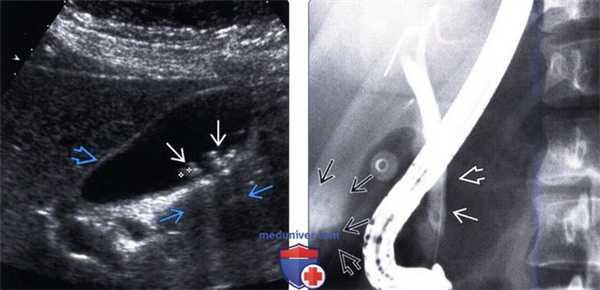

(Левый) На рисунке показаны множественные не вызывающие обструкции конкременты дистальной части общего желчного протока и желчного пузыря.

(Правый) На продольном УЗ срезе в просвете общего желчного протока определяется отбрасывающий тень эхогенный очаг, соответствующий конкременту. Общий желчный проток лежит спереди от печеночной артерии и воротной вены. Печеночная артерия идет между воротной веной и общим желчным протоком. (Левый) Дальше в каудальном направлении в просвете общего желчного протока в виде эхогенных отбрасывающих тень очагов определяются еще несколько конкрементов, тянущихся до уровня головки поджелудочной железы (цветовая допплерография помогает дифференцировать желчные пути от прилетающих сосудов).

(Правый) В дальнейшем при рентгеноскопии - эндоскопической ретроградной холангиопанкреатографии в просвете общего желчного протока определяется несколько дефектов заполнения, соответствующих конкрементам.